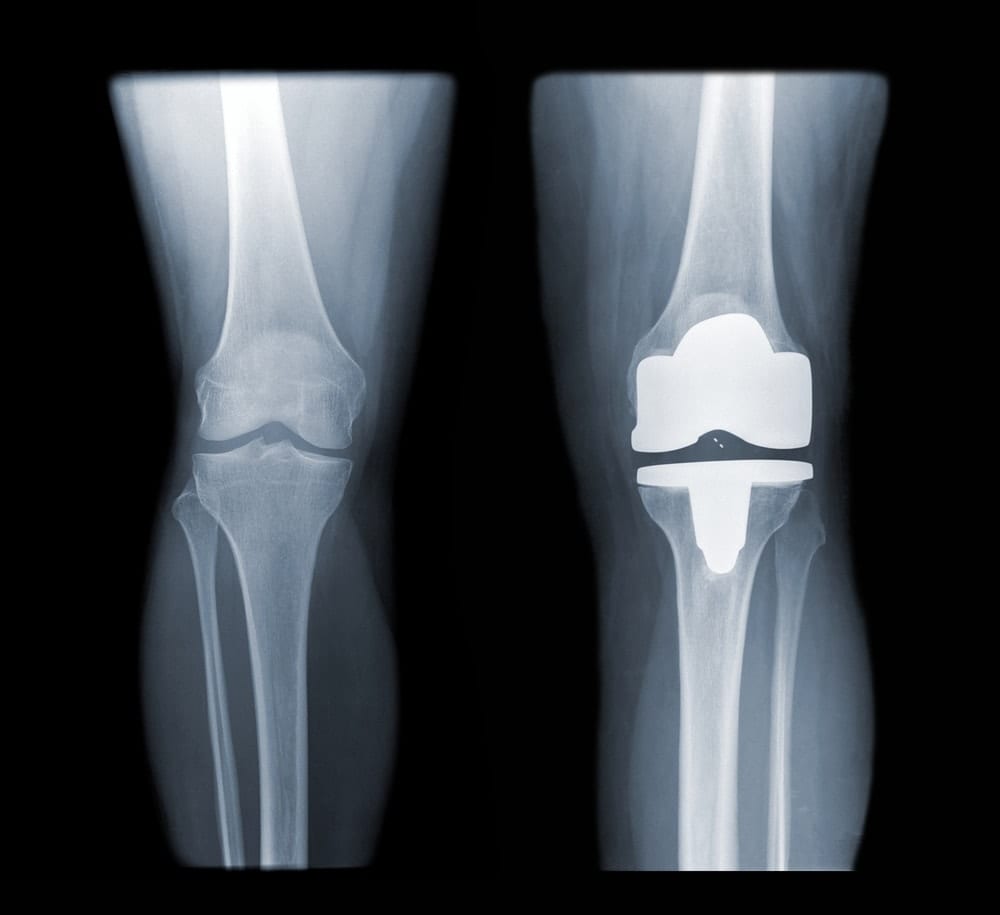

החלפה מלאה של מפרק הברך – Total Knee Replacement:

ניתוח קונבנציונלי: ניתוח החלפה מלאה של מפרק הברך Total Knee Replacement – הוא הניתוח השכיח ביותר ובו מדווחים אחוזי ההצלחה המשמעותיים ביותר – שיעור הצלחה של מעל 90%. בניתוח מוחלפים המשטחים המפרקיים השחוקים במשתל מתכתי. אורך החיים של המשתל הוא מעל 15 שנה ורמת הסיבוכים בניתוח, באופן כללי, נמוכה.

אורך החיים של משתל הברך הוא בממוצע 15 שנה. בתום תקופה זו המשתל המלאכותי, בדומה לכל מבנה מכאני אחר, מתרופף ואז נוצר צורך להחליפו במשתל אחר, ייעודי למצב זה, הנקרא משתל רביזיה. המשתל גדול יותר והניתוח מטבע הדברים מורכב יותר.